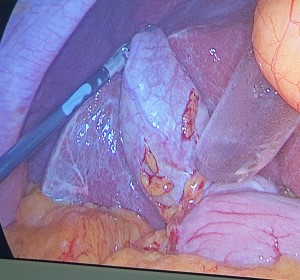

KARACİĞER KANSERLERİ NELERDİR,NASIL TEDAVİ EDİLİRLER?

Karaciğer karnın sağ üst bölgesinde,diafragmanın altında yerleşmiş 1.2-1.5 kg. ağırlığında bir organdır.Sağ ve sol olmak üzere 2 lobdan meydana gelmiştir. Sindirim işlemlerinde görev alır(yağların sindirimine yardımcı olan safrayı üretip salgılar) ve sindirim işlemleri sonucu ortaya çıkan, vücut için zararlı(toksik) bazı maddelerin elimine edilip(zararsız hale getirir) atılmasını sağlar.Kanın pıhtılaşması için gerekli olan bazı pıhtılaşma faktörlerini yapar.Ayrıca...